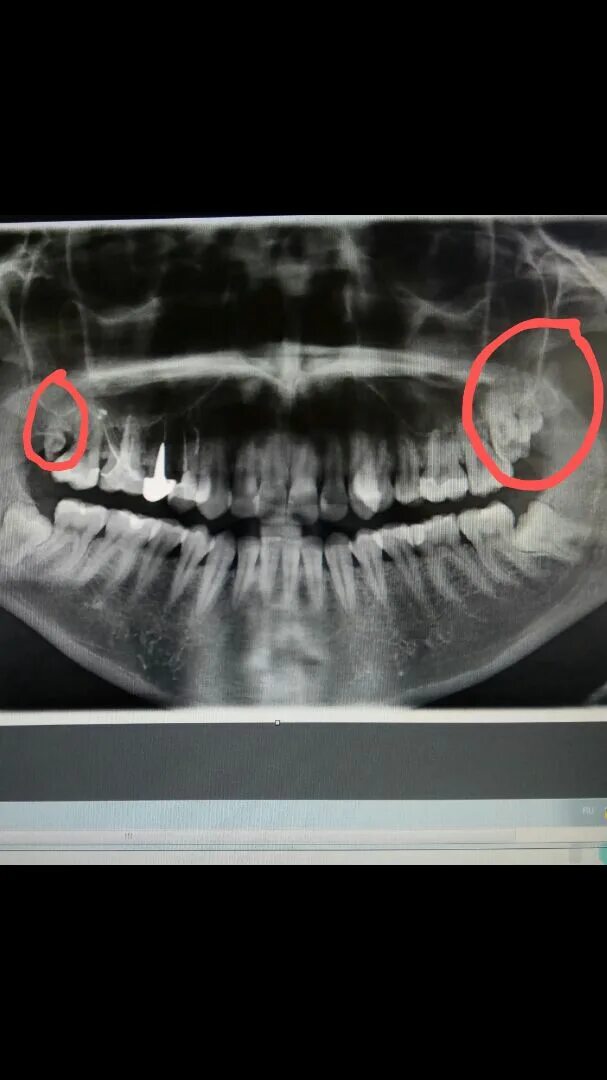

Могут ли быть 9 зубы